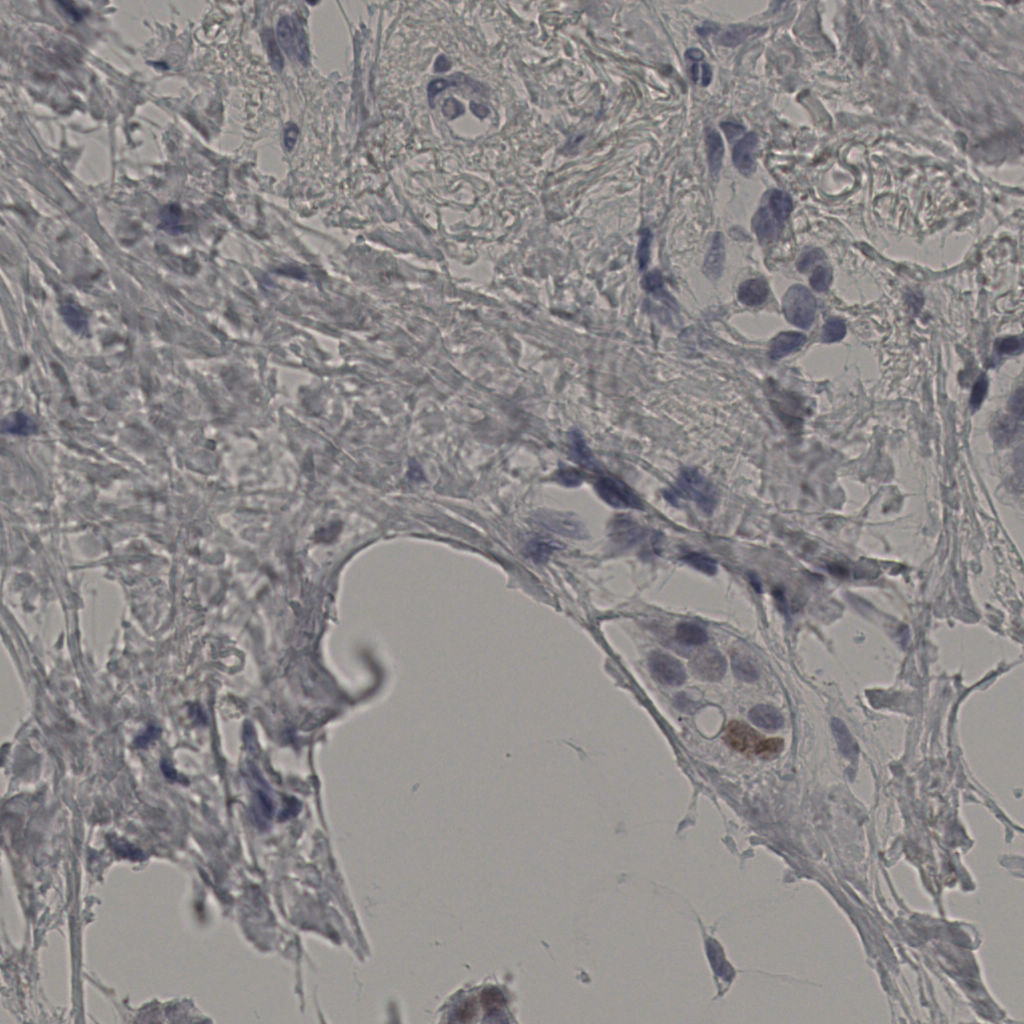

20240398Ki-67.ndpi

slice_42_31_x37632_y27776.png

slice_42_31_x3763...